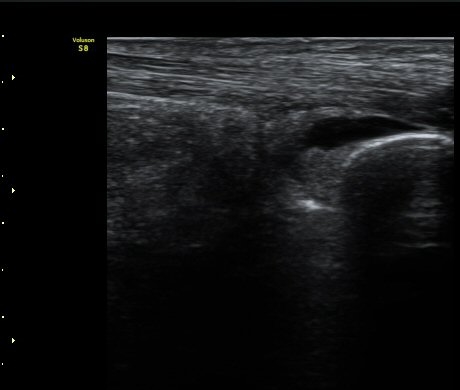

¾ÆÅ³·¹½º ÈûÁÙ Á¾´Ü¸é»ó¿¡¼ ÈûÁÙ Ãø¸éÀ¸·Î Áֻ縦 ½ÃÇàÇÏ°í ¾àÁ¦°¡ º´º¯¿¡ Á¤È®È÷

ÁÖ»çµÇ´Â °ÍÀ» ÃÊÀ½ÆÄ·Î È®ÀÎ(µ¿¿µ»ó)